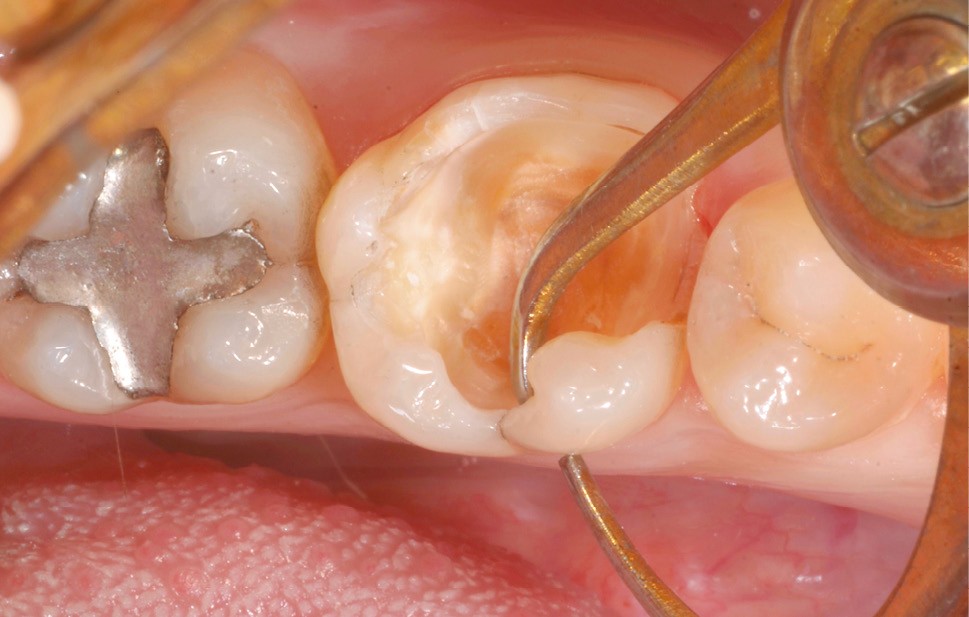

Lors de la préparation d’une cavité pour inlay/onlay, il est fréquent d’être confronté, en fin de nettoyage, à la présence d’une ou plusieurs parois résiduelles dont la résistance mécanique paraît douteuse du fait de leur localisation ou de leur épaisseur. Les parois épaisses (+ de 2 mm) peuvent généralement être conservées (cas clinique 1) et les parois fines (- de 1 mm) doivent généralement être recouvertes. Un inlay (en composite ou en céramique) est alors réalisé. Il doit avoir lui même, au final, une épaisseur globale minimale de 2 mm pour assurer sa résistance mécanique intrinsèque à la mastication. Si un recouvrement cuspidien est indiqué, la réduction occlusale doit donc se faire sur 2 mm de hauteur au minimum [1, 2].

S’il est impossible de connaître avec certitude le risque de fracture d’une cuspide, l’objectif de cet article est de donner des éléments objectifs de prise de décision de la conservation ou du recouvrement des parois d’épaisseur moyenne à la fin du nettoyage cavitaire selon la dent, l’occlusion, la forme et le volume de la cavité, la présence ou non de dentine, la vitalité ainsi que l’incidence esthétique.